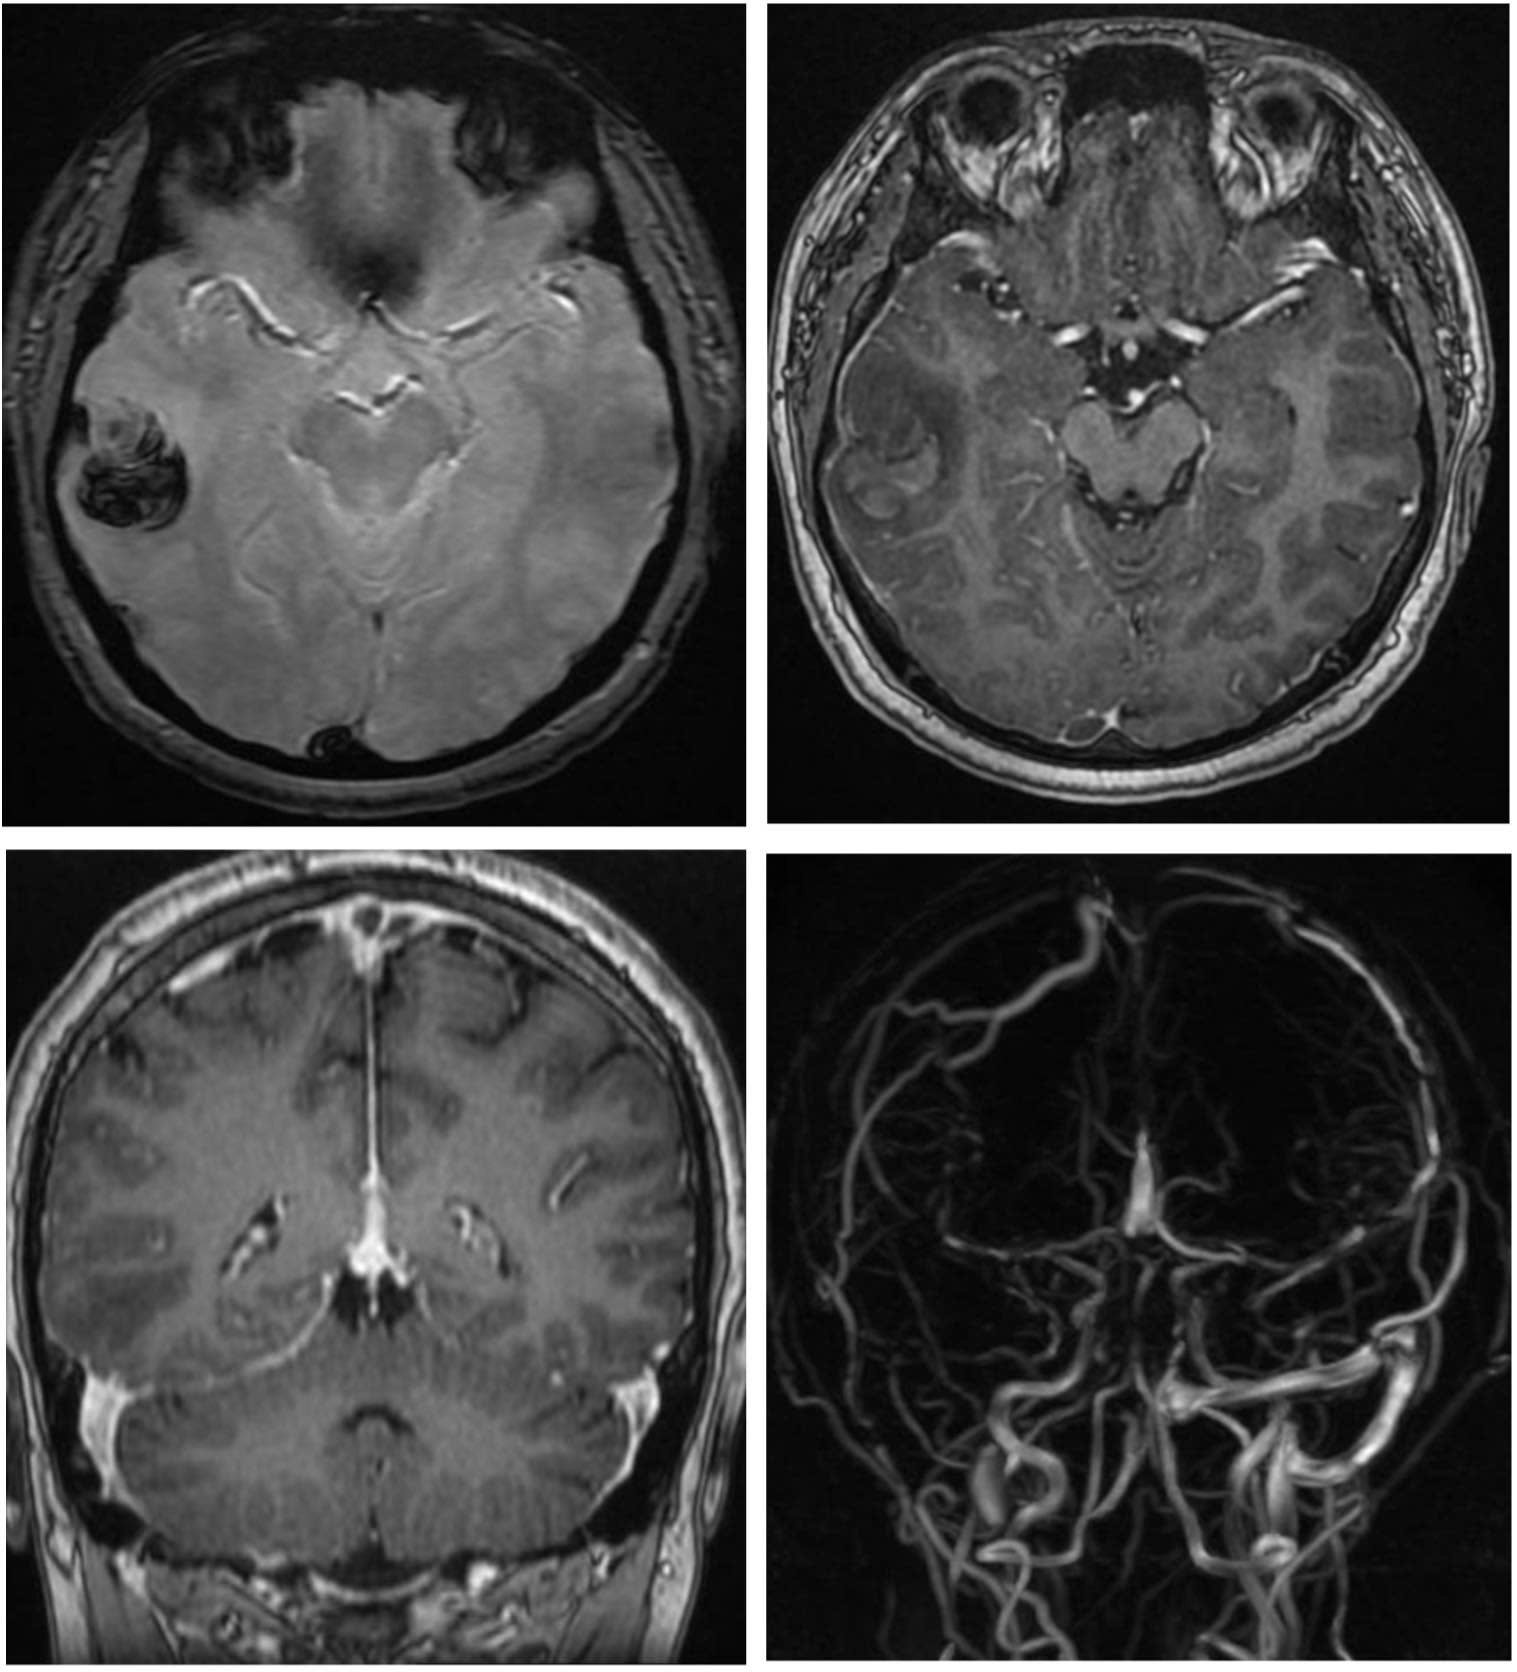

Hút shisha, nam thanh niên 22 tuổi đột quỵ